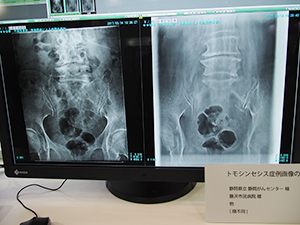

●「BENEO-Fx」のトモシンセシス撮影の臨床例を画像で紹介

一般撮影コーナーでは,トモシンセシス機能やエネルギーサブトラクション撮影機能などを搭載したデジタルX線画像診断システム「FUJIFILM DR BENEO-Fx」,ロングサイズパネル「CALNEO GL」と電動式立臥位撮影台「FM-PL1」を組み合わせた長尺撮影システムなどを展示した。

BENEO-Fxのトモシンセシス機能では,振り角は30°(15°×2),撮影時間は8秒で40枚の撮影を行う。再構成によって断層画像を生成してボリュームで観察できる。通常の一般撮影に連続して撮影でき,臥位だけでなく立位での撮影も可能で,低被ばくで患者の負担も少なく新たな診断情報が得られることが期待される。BENEO-Fxのコーナーでは,トモシンセシスの症例画像として“仙骨不顕性骨折(骨粗鬆症による脆弱性骨折)”“腰椎骨折”“播種による癌性胸膜炎”などの画像を提示し胸腹部領域でのトモシンセシスの有用性を紹介した。

播種による癌性胸膜炎の症例では,心臓裏の腫瘤が明瞭に描出されている。CTでは臥位で撮影するため胸水が貯留している場合に腫瘤部分にかぶり辺縁が不明瞭になる場合があるが,BENEO-Fxのトモシンセシス撮影では,立位撮影によって胸水がかぶることなく明瞭に描出でき,撮影線量も低いことからフォローアップなどで有効に利用できることが期待される。

トモシンセシスの症例画像:播種による癌性胸膜炎 |